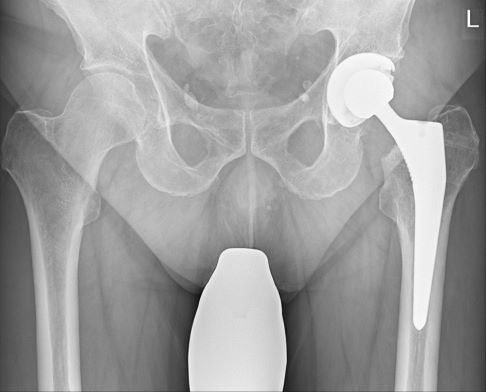

Operative Therapie mit Hüftprothese

In den meisten Fällen entscheidet sich der Orthopäde für eine operative Behandlung des Oberschenkelhalsbruches. Man unterscheidet hüftkopferhaltende und hüftkopfersetzende Verfahren zur Therapie der Oberschenkelhalsfraktur. Mithilfe einer Hüftprothese kann der Patient schnellstmöglich die Folgen eines Oberschenkelhalsbruches überwinden. Bei einer Hüftprothese ist das betroffene Bein bereits am Tag nach der OP wieder belastbar. Langdauernde Bettruhe ist nicht erforderlich. Unmittelbar nach der Hüftprothesenoperation beginnt der Patient mit krankengymnastischen Übungen, um die Mobilität zurückzuerlangen.

Die Versorgung des Oberschenkelhalsbruchs mit einer Endoprothese kommt vor allem für ältere Patienten (> 65 Jahre) infrage. In einigen Fällen ist eine Hemiprothese (Teilprothese) ausreichend. Zeigt das Hüftgelenk allerdings Anzeichen einer Arthrose, ist eine Vollprothese das Mittel der Wahl.